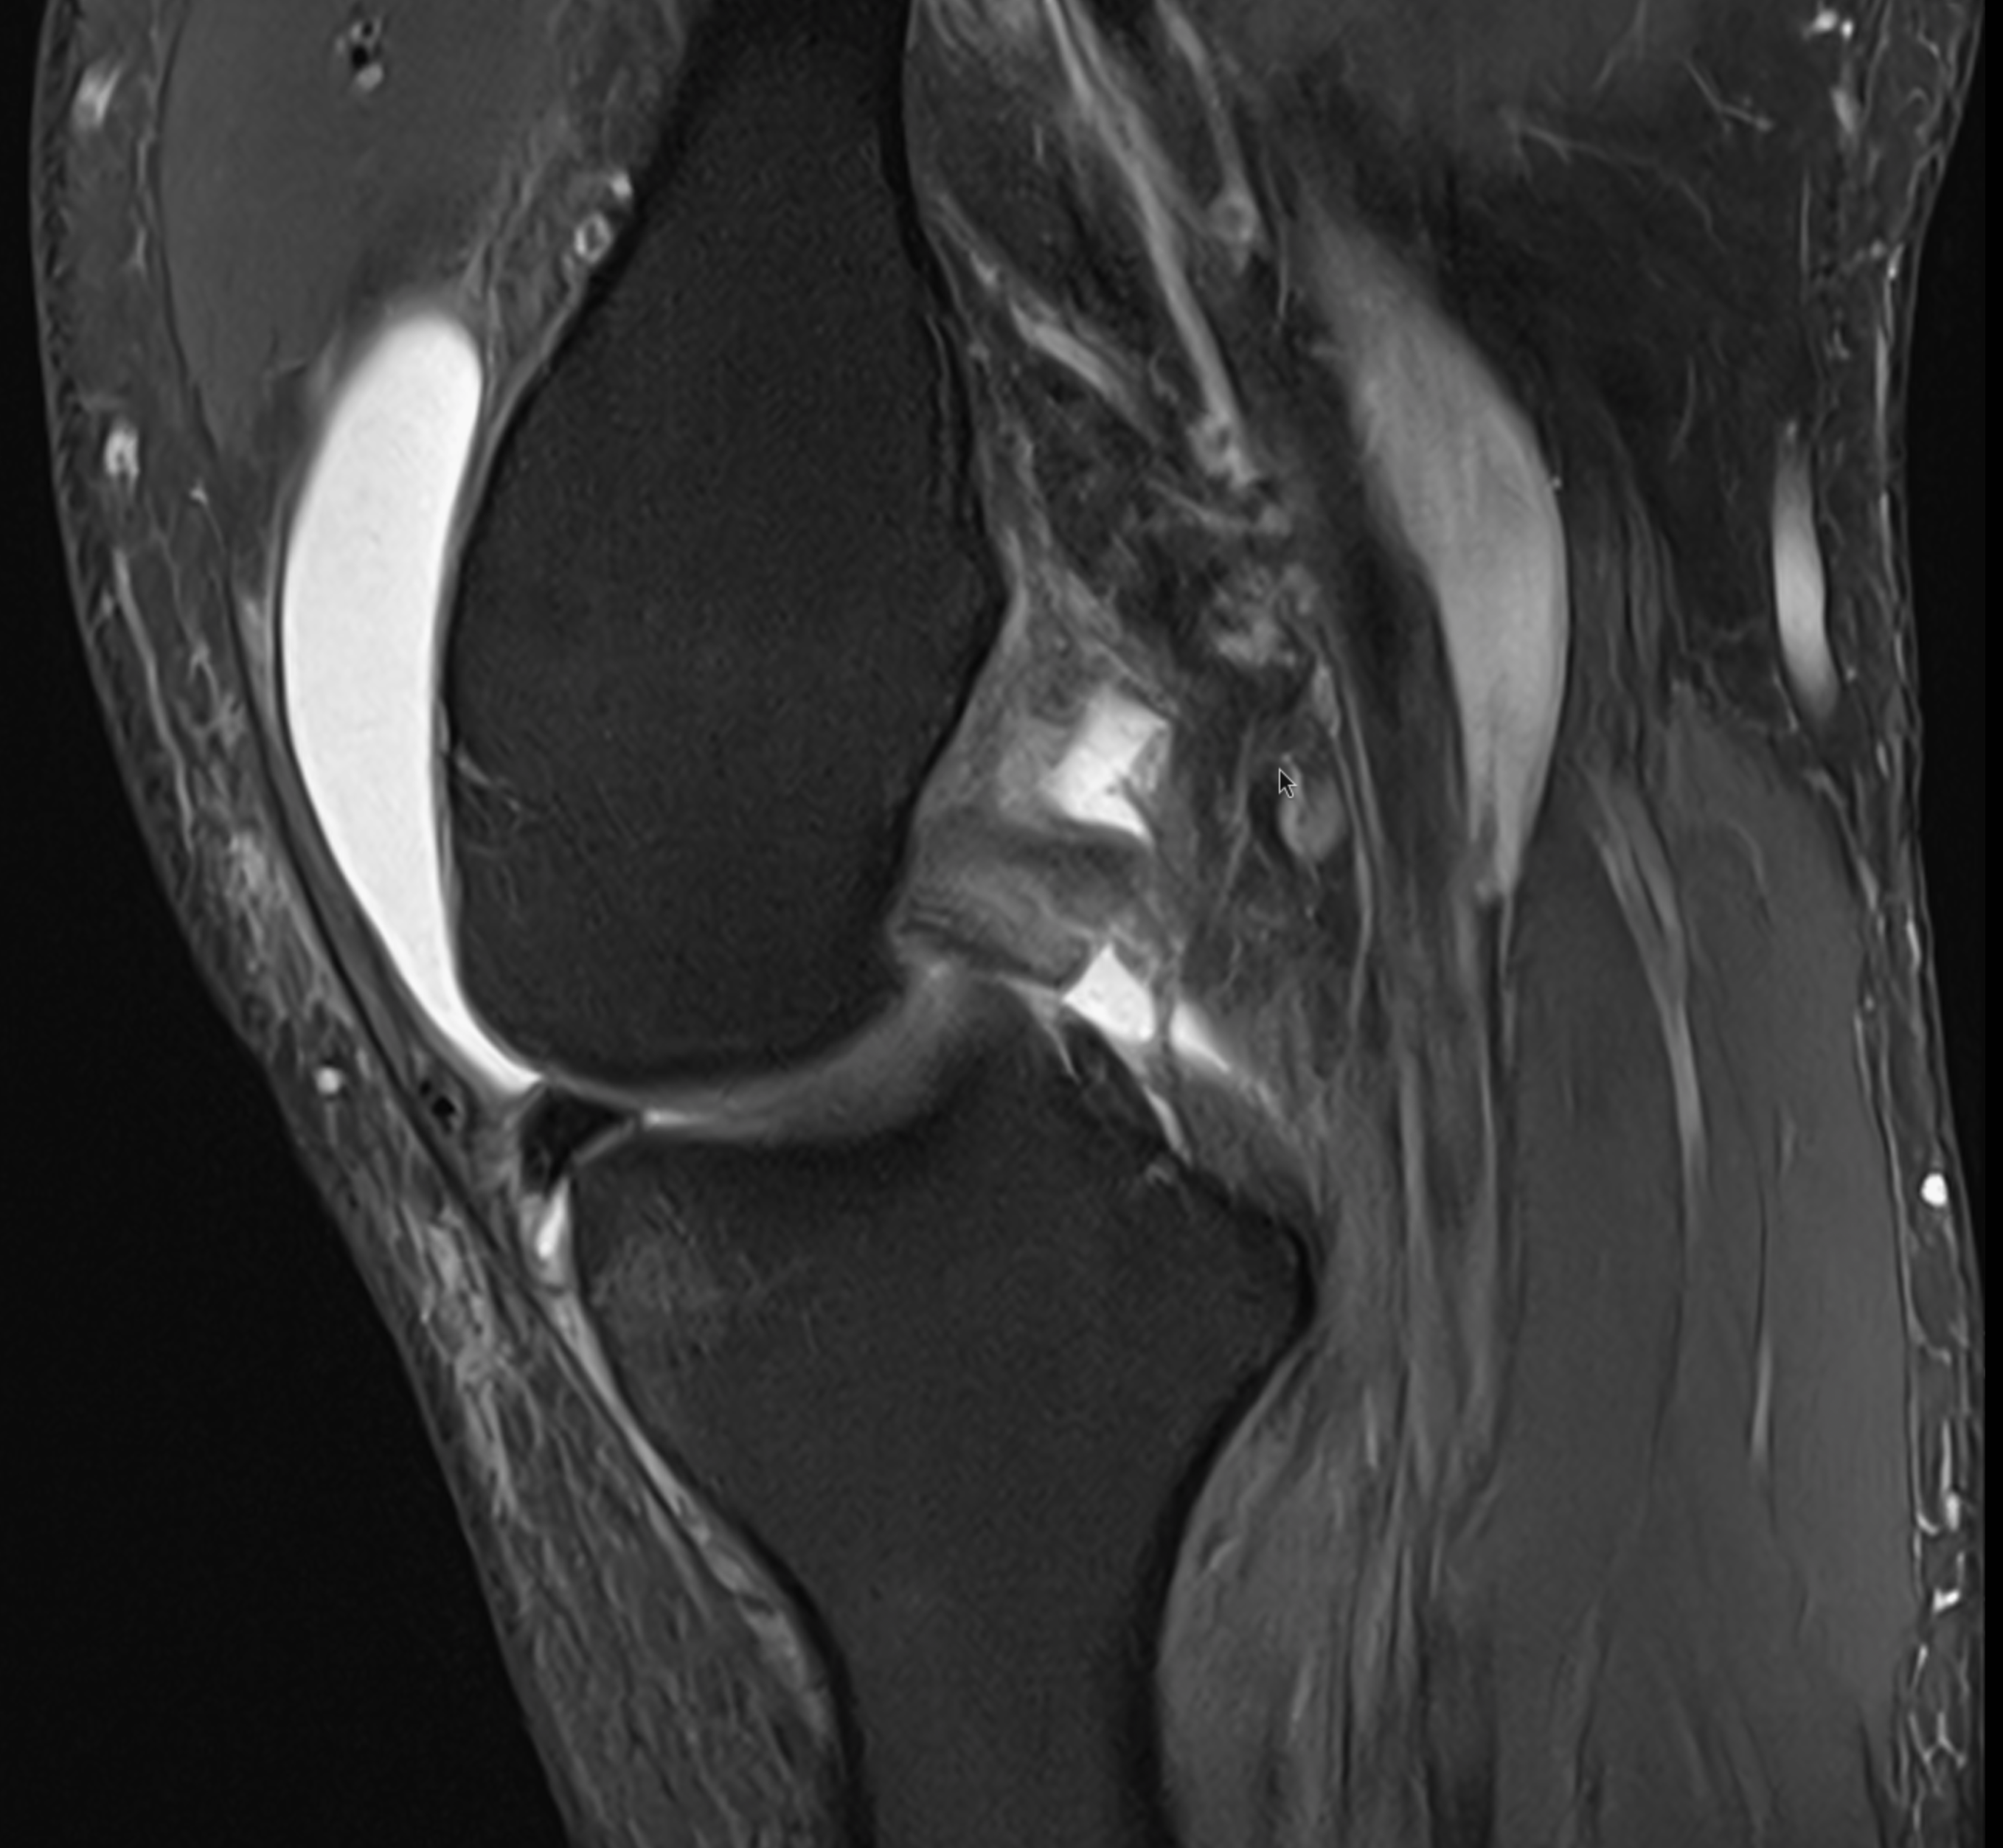

Torn PCL